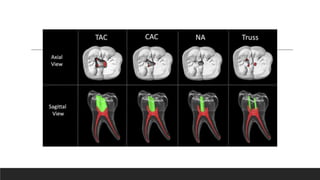

The newer concepts in access cavity preparation includes

•Conservative endodontic access cavity

•Ultra conservative access cavity / ‘Ninja'

•Orifice – directed dentin conservation access cavity / Truss

•Caries driven / Restorative driven

Conservative access cavity

•By David Clark and John Khademi

•Lessen the tooth structure removal.

•Helps the long time survival & function of root canal treated tooth.

•Here, the teeth are accessed at the central fossa and they are extended out to discover canal orifices. This

aids in protecting the pericervical dentin and a part of the chamber floor.

Ultra conservative access cavity/

Ninja method

•Here, an oblique projection is made towards the central fossa of the root canal orifices

•This projection is made parallel with the enamel cut of 90 degree or more to the occlusal plane

•This makes simpler to discover the canal orifices from different visual angulations

•Limited line of vision, incomplete removal of infected pulpal tissue is the main limitation leading to failure

of endodontic treatment.

Orifice- Directed Dentin Conservation

Access Cavity / Truss

’

•Separate cavities are made to approach the canals

•The point of this methodology is to preserve dentin with the minimally invasive approach i.e. leaving

a truss of dentin between the two cavities that have been prepared

•The restricting components of this methodology which are past the operator’s control are position of

tooth, patients mouth opening capability, degree of calcification & other patient related variables